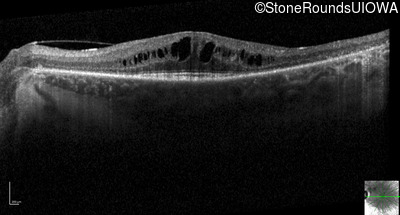

Optical Coherence Tomography - Right - 20/40 +2

Exemplar / OCT Stack

OCT Stack